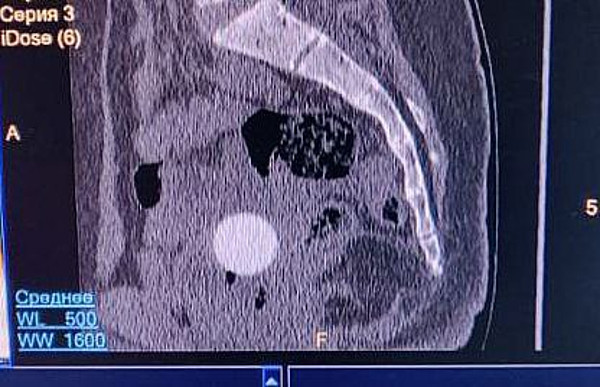

< < <photo_2_2025-10-09_14-14-17photo_3_2025-10-09_14-14-17photo_5_2025-10-09_14-14-17

photo_5_2025-10-09_14-14-17.